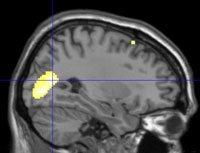

Methamphetamine users in Cape Town,

South Africa were examined using

magnetic resonance imaging.

In meth users, an area of the brain called

the putamen was enlarged, indicating an

increased desire for the drug.

Scans courtesy of Deborah Yurgelun-Todd

Subjects were tested using magnetic resonance imaging (MRI) and functional MRI, which measures blood flow and metabolic changes. Forty subjects were scanned: 10 were tik and pot users, 10 used cannabis and 20 were controls.

From the structural imaging or MRI data, researchers found that, in the meth-pot users, a part of the brain called the putamen was enlarged. “This area has been related, in other studies as well, to reward circuitry, or the desirability of the drug,” said Yurgelun-Todd. “Changes in this region secondary to drug abuse initiation may be associated with reduced sensitivity to the rewarding properties of drugs and lead to increased drug taking.”